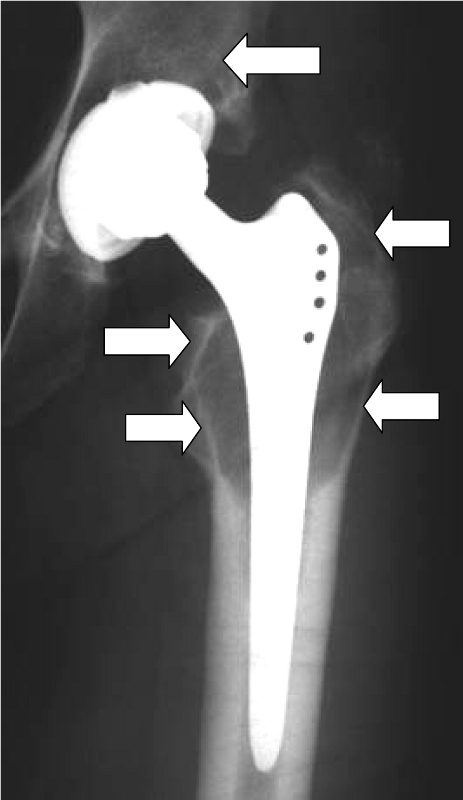

Skin tests (epicutaneous tests) do not show a clear correlation to the reaction of a joint to the implant, so that even skin testing for a metal or cement allergy cannot give a 100% indication. Therefore, in case of doubt, it is necessary to perform a tissue biopsy from the affected joint to provide the appropriate level of certainty. In the case of an allergy, lymphocyte infiltrates are frequently found in these tissues.

Beschichtete KnietotalendoprotheseDiffuse Lymphozyteninfiltration in der GelenkkapselOsteolyse um einen Prothesenschaft (Pfeile)